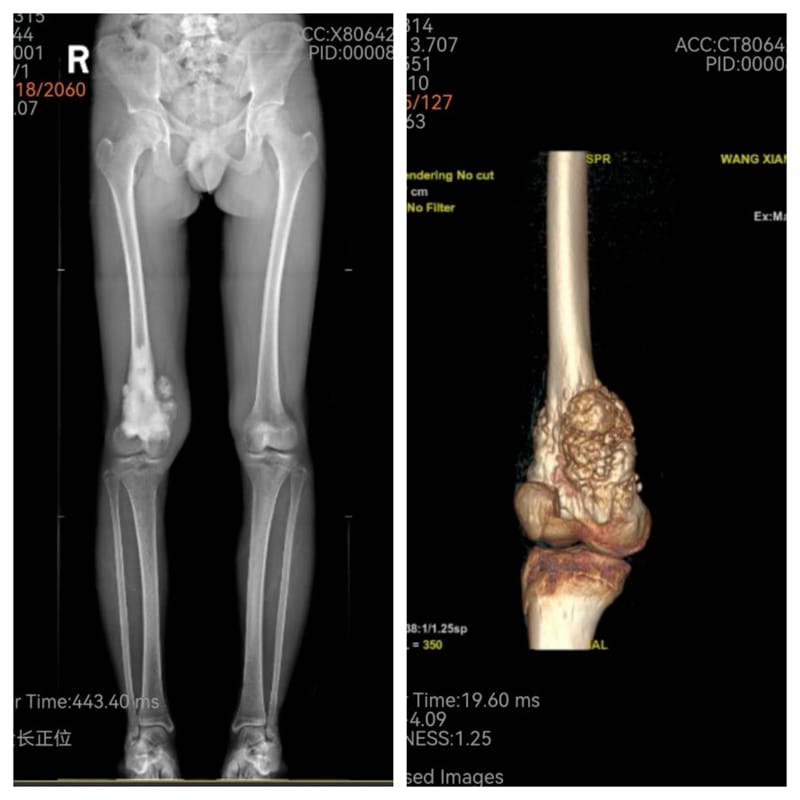

患者小王,17岁,因右大腿肿痛10个月不能行走,确诊为“右大腿股骨骨肉瘤”。入院后,骨科主任、关节外科病区主任、主任医师吴军团队结合患者肢体“病变范围发展快、范围大,靠近膝关节”的特点,为其制定了“先放化疗,再手术,再规范化疗”的治疗方案,在肿瘤科协作下,患者完成放化疗疗程后转骨科关节外科病区手术。放化疗后,尽管小王肿瘤有缩小,但肿瘤仍然侵及整个股骨下端、股骨髁和股中间肌,关节结构破坏严重。经过反复比对、测量,并利用电脑模拟切除肿瘤后关节重建范围等术前准备,吴军团队凭借娴熟和丰富的综合骨科经验,在完整保留股内外侧肌、股直肌、股骨近端、胫骨平台和神经血管的基础上,完整切除波及股骨及关节的肿瘤,按术前规划成功实施了股骨下段和膝关节的假体置换和重建。

术前,化疗后

手术完美重建股骨、膝关节